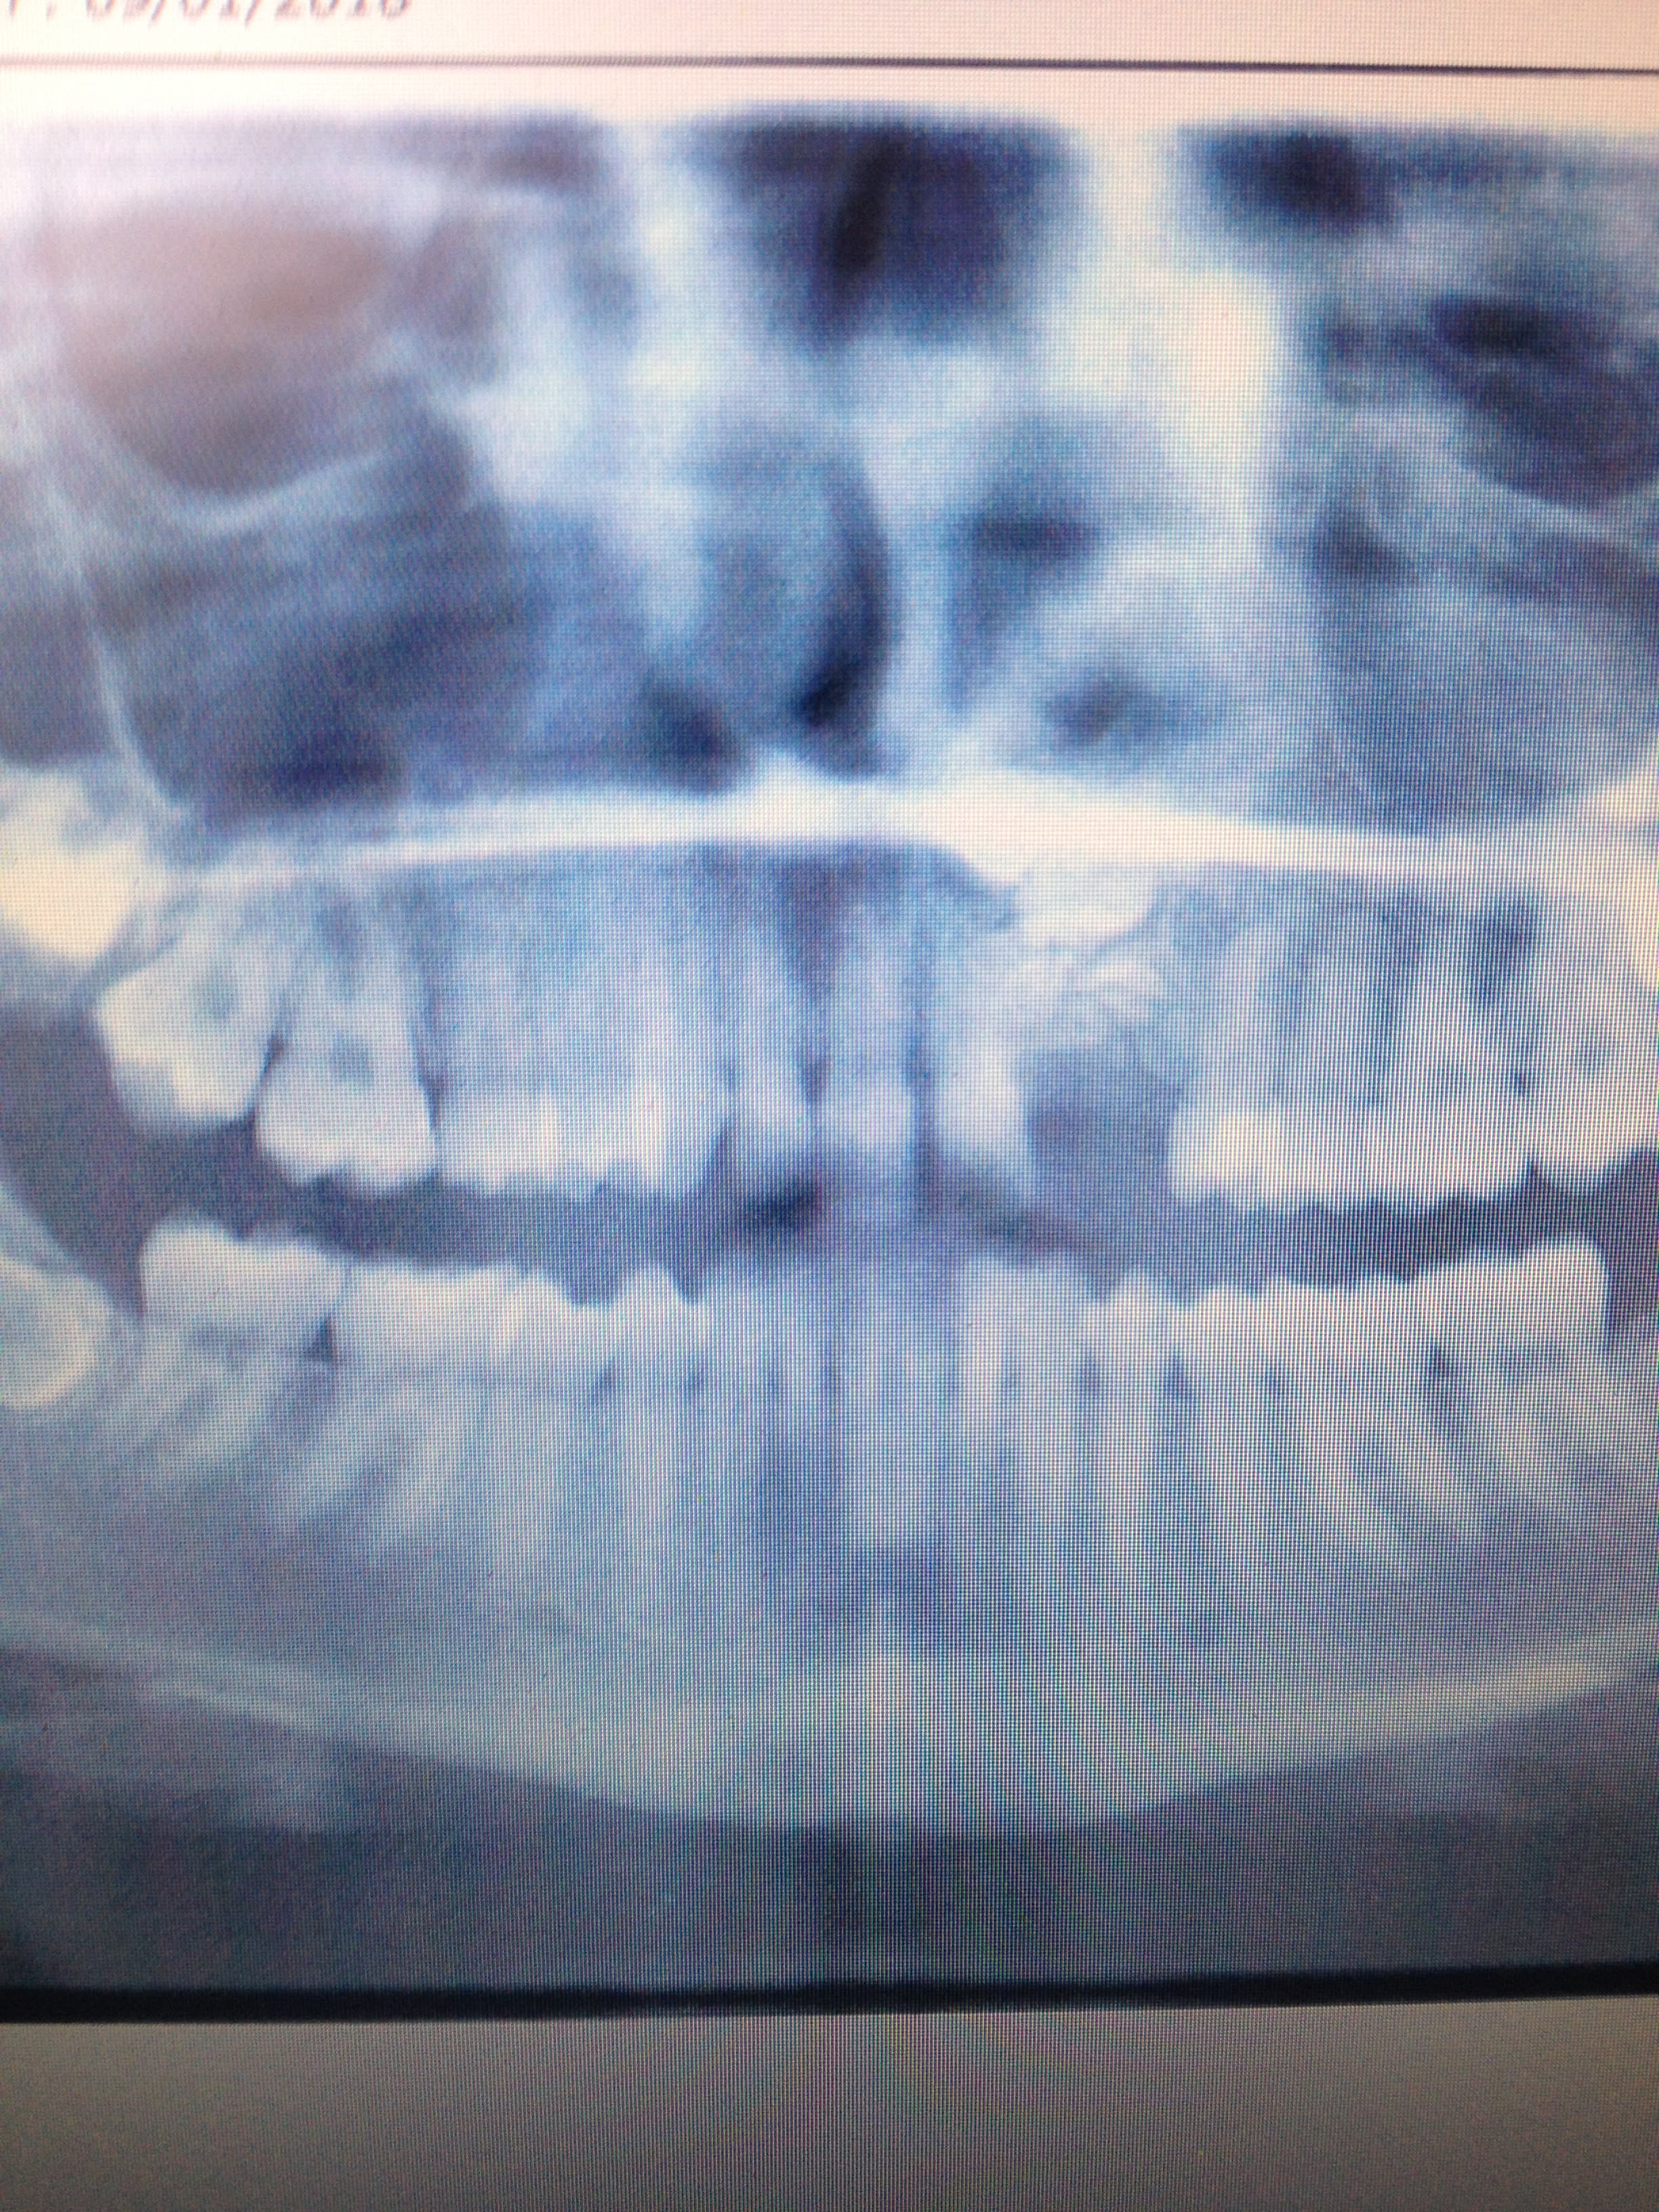

Cas d'odontome composé

Pas difficile mais faut pas en oublier!